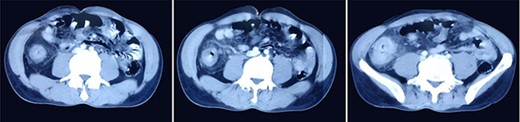

A 51-year-gentlemen and a smoker visited our institute with a history of abdominal pain, predominantly over the umbilical area, constant in nature, associated with anorexia, back pain and occasional chest pain for about 1 year. Besides pallor, other examination findings were grossly normal. His body mass index was 17 mg/m2. The comprehensive blood panel, renal function test and liver function test yielded normal findings. USG of abdomen and pelvis showed thickened cecum and terminal ileum with few adjacent mesenteric lymph nodes likely to be an infective/inflammatory pathology along with coexisting right nephrolithiasis. Intestinal TB was suspected and further investigations were done but reported negative Mantoux test, AFB smear and normal chest X-ray findings. Colonoscopy showed ulcero-proliferative growth in the cecum and descending sigmoid junction with punch biopsy from the cecal growth showing mitotic lesion suggestive of carcinoma colon (Fig. 1). A repeat colonoscopic biopsy of the cecal growth suggested diffuse active colitis. Computed tomography (CT) revealed segmental asymmetrical circumferential mass-like wall thickening of the cecum and ascending colon over the length of 7.6 cm causing luminal narrowing with enhancing soft tissue extension into the adjacent pericolic fat with loss of fat plane with the right psoas major muscle, pericolic fat stranding along with thickening of adjacent peritoneal lining (Fig. 2). The presence of multiple homogeneously enhancing pericolic, ileocolic, superior mesenteric artery and para-aortic groups of lymph nodes suggested colon carcinoma (T4aN2b). It also revealed a small iso-dense lesion showing homogeneous enhancement on the arterial phase in segment VII of the right lobe of the liver abutting capsule suggestive of metastasis. Carcinoembryonic antigen (CEA) was found to be slightly raised (7 ng/dl).

Colonoscopy images showing ulcero-proliferative growth in the cecum and descending sigmoid junction.